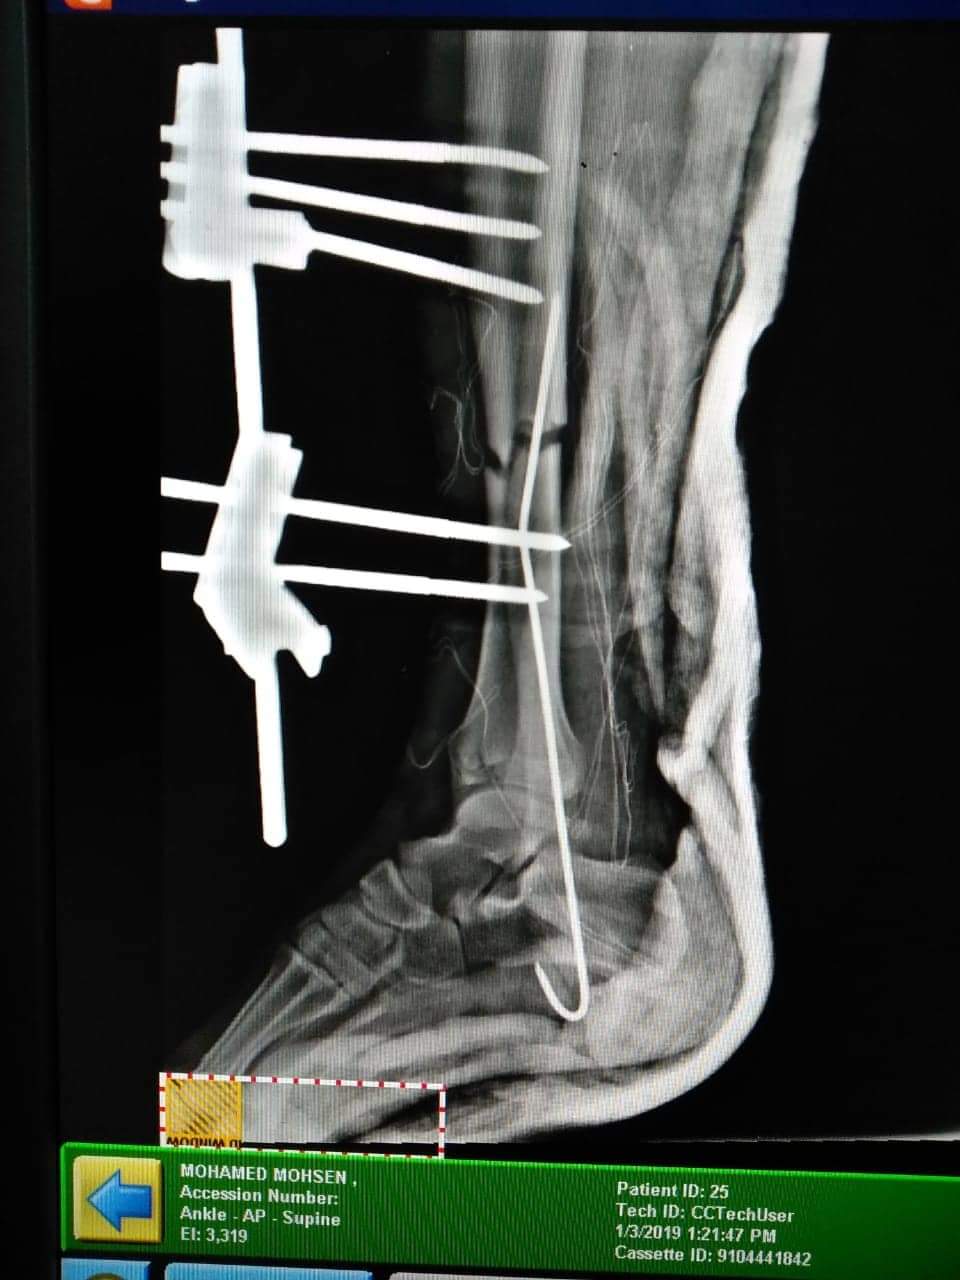

نجاح جراحة تثبيت مؤقت لكسر مضاعف بالساق في مستشفى طور سيناء

نجح الفريق الطبي بمستشفي طور سيناء العام في إجراء جراحة تثبيت مؤقت لكسر مفتوح من الدرجة الثالثة بعظمتي الساق اليمني لمصاب بواسطة مثبت خارجي .

حيث حضر المصاب لقسم الطوارئ وبتوقيع الكشف الطبي عليه وعمل الفحوصات واﻷشعات الﻻزمة تبين أنه يعاني من كسر مفتوح ( مضاعف ) من الدرجة الثالثة بعظمتي الساق اليمني مع تهتك بالعضلات وفقد جزء كبير من الجلد .

وتم تحضر المصاب للعمليات و عمل تنظيف وتطهير جيد للجرح المتهتك وعمل تثبيت مؤقت للكسر المضاعف بواسطة المثبت الخارجي .

تمت العملية بواسطة  الفريق الطبي الذي ضم الدكتور هيثم  أمين، والدكتور معتز حمدي  أخصائي العظام بالمستشفي، والدكتور  سامي عبدالرازق  إستشاري التخدير.